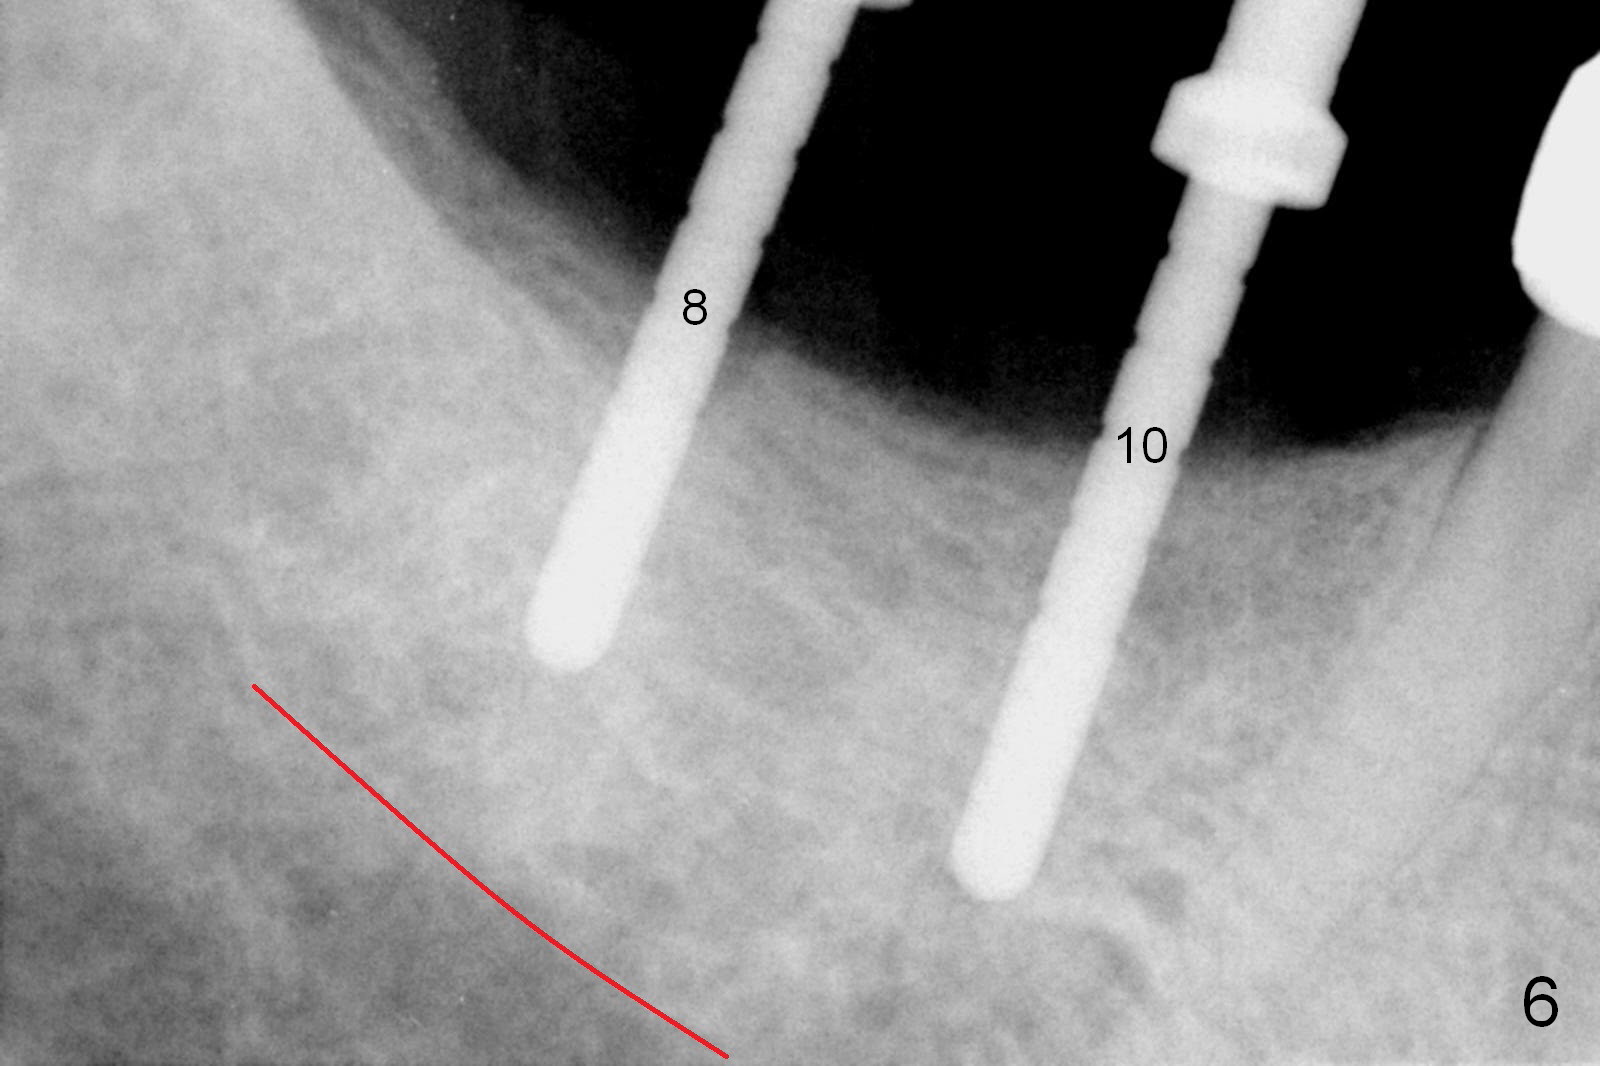

One month later, the patient returns for #30 and 31 implant placement. As planned, the initial depth is 10 and 8 mm (Fig.6). What is unexpected is deficiency in ridge width. Narrower implants (as compared to those on the left) are placed (Fig.7: 4.5x12 and 4.5x10 mm). With shorter implants, the implants are later placed deeper (as shown by arrows in Fig.7) so that almost all of the microthreads are buried in the bone. It is expected that there is less chance of thread exposure postop. The later turns out to be true 3.5 months postop (Fig.8 with 6.8x5(3) mm abutments). It appears that the abutment margin is supragingival (white dashed line: gingival margin) and should be trimmed prior to impression. Or change the abutments to ones with shorter cuff. It may be so for those at #18 and 19 (Fig.9: 4 months postop). Custom full arch trays will be used for impression with bite registration. In fact the mesial margin of #19 abutment is ~ 2 mm subgingival. A longer-cuff abutment is used (6.8x5(3) mm) at #19 before impression.